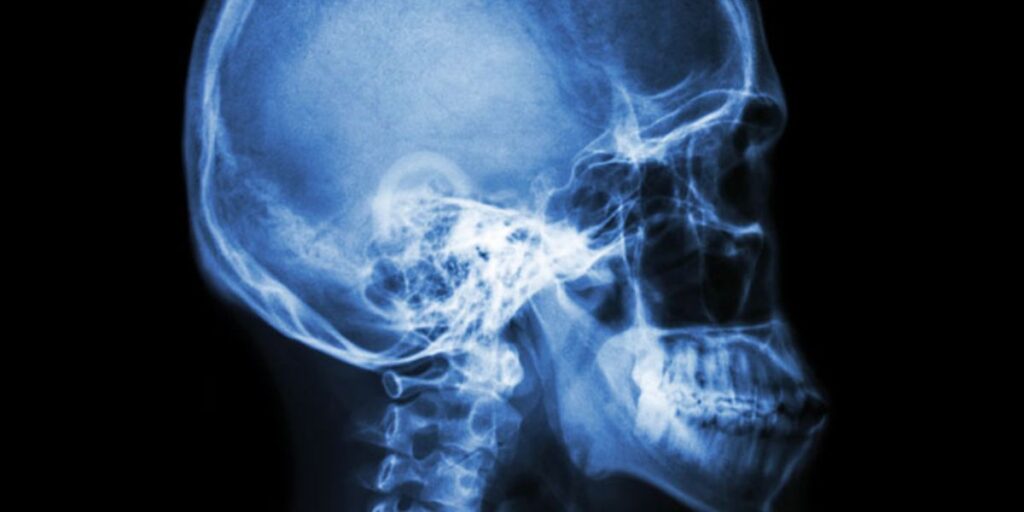

La RX Sella Turgica, o radiografia della sella turcica, è un esame diagnostico che permette di ottenere immagini dettagliate della sella turcica, una piccola depressione ossea situata alla base del cranio. Al suo interno si trova l’ipofisi, una ghiandola endocrina essenziale per la regolazione di numerosi processi fisiologici, come il metabolismo, la crescita e la funzione riproduttiva.

L’esame viene svolto in modo semplice e non invasivo presso il Poliambulatorio S-Medical Group di Sora. Il paziente viene fatto accomodare sul lettino radiografico e posizionato in maniera tale da consentire la visualizzazione ottimale della sella turcica. Attraverso l’utilizzo di raggi X, vengono catturate immagini da diverse angolazioni per garantire una valutazione completa della struttura ossea e dei tessuti circostanti. L’intero procedimento dura generalmente tra i 15 e i 30 minuti e non richiede anestesia.

La RX Sella Turgica consente di identificare numerose condizioni patologiche che interessano la sella turcica e l’ipofisi. Le immagini ottenute possono rivelare: